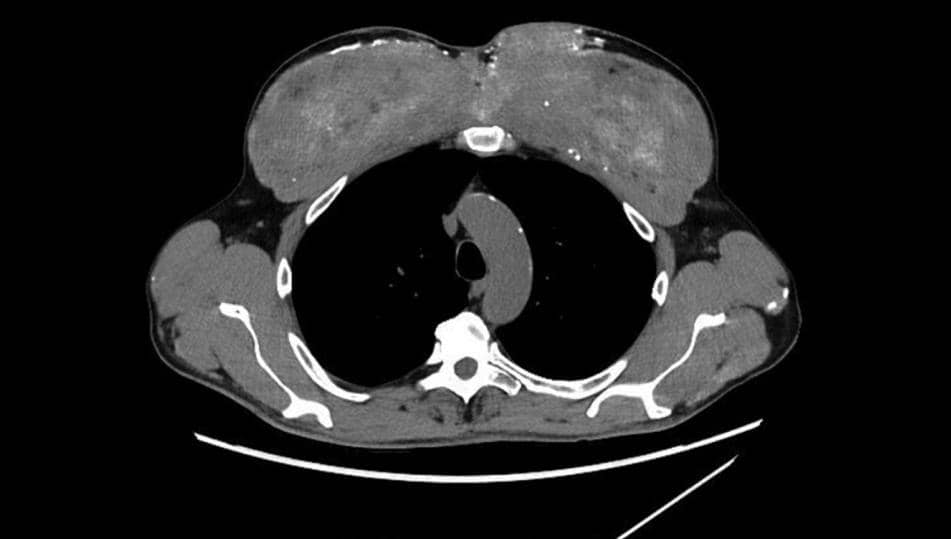

الفحوصات المخبرية أظهرت ارتفاعًا خطيرًا في مستويات الكرياتين واليوريا، ما دلّ على تدهور واضح في وظائف الكلى، إضافة إلى مستوى مرتفع من الكالسيوم وصل إلى حد يهدد القلب والدماغ. وأظهرت صور الأشعة انتشار تكلسات واسعة في الكليتين والبنكرياس والمعدة، كما ظهرت ندبات غير طبيعية في الرئتين، بينما بدت عضلات الصدر شبه متصلبة.

خزعة أُخذت من إحدى العضلات المتضررة كشفت الحقيقة: المادة التي ملأت العضلة كانت زيت السينثول، وهو زيت يستخدمه البعض لتكبير العضلات شكليًا، ويتسبب غالبًا في تفاعلات التهابية طويلة الأمد. ومع مرور السنين تراكمت حوله طبقات كثيفة من التكلس، قبل أن يبدأ الكالسيوم بالتسرب إلى الدم ويتسبب في الاضطراب الخطير الذي يعاني منه المريض.